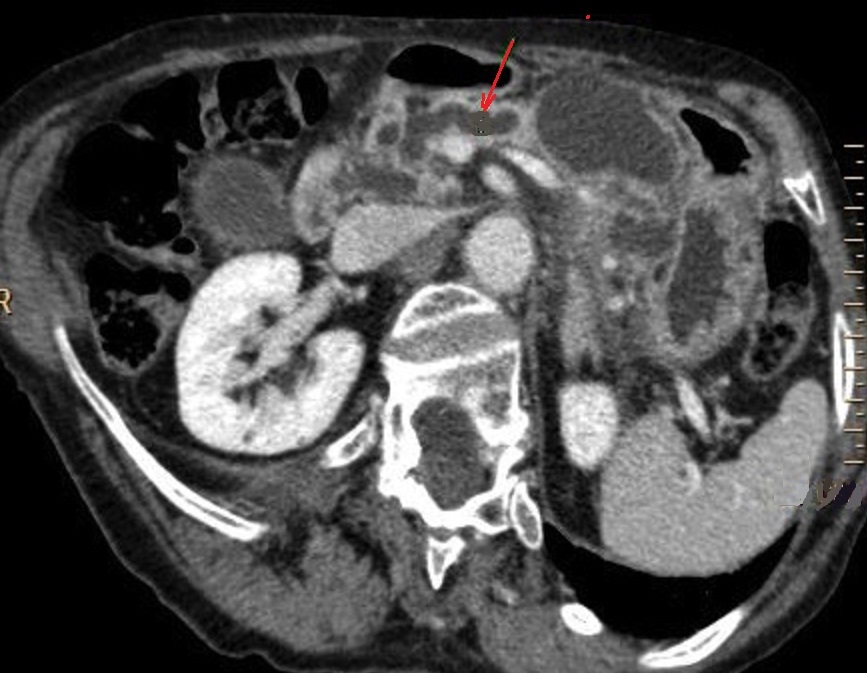

Image

radiologique TDM d'une TIPMP type canaux

secopndaire du cord pancreas a aspect lesionnel de

kyste liquidienne ovalaire hypoidensite a bord

regulier , fine en vue tres nette du corp du

pancreas ( fleche rouge ), sa paroi ne se

rehaussement apres injection de contras

intraveineuse . Image radiologique TDM plus C+

en coupe axiale . |